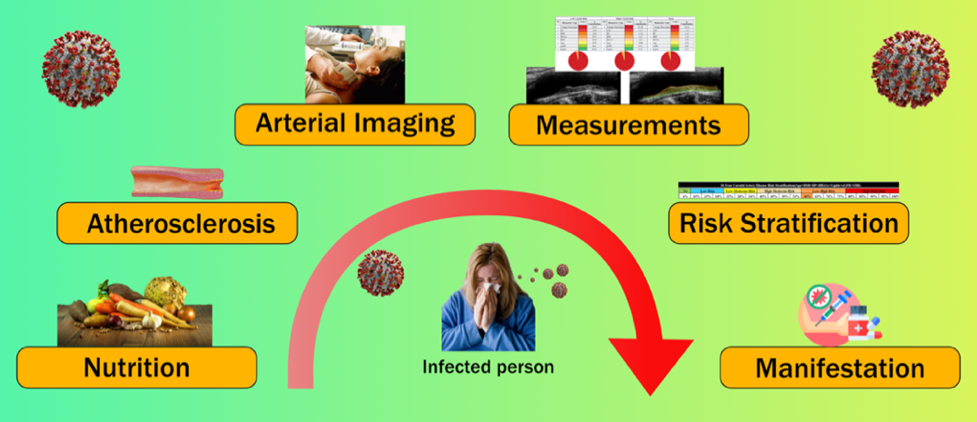

Fig. 1.

Fig. 1.Global view and CVD stages for risk assessment.

CVD risk assessment becomes even more important in the era of COVID-19 since it has a great deal of impact on underlying conditions, complications of infections, and other diseases [42]. A high incidence of thromboembolic events has been found in patients with COVID-19 [43]. It is also observed that COVID-19 leads to the worsening of conditions in the presence of CVD [44, 45, 46]. We will focus on the molecular pathways that can cause epithelial dysfunction and atherosclerotic plaque formation leading to the risk of major cardiovascular events during COVID-19.

Thus the overall objective of this study is to understand how (a) nutrition affects the formation of atherosclerosis and plaque formation, (b) the role of low-cost surrogate CVD such as carotid ultrasound-based screening which can help in effective AI-based risk stratification and monitoring the atherosclerotic disease, (c) manifestations types, and (d) study the effect of COVID-19 on the CVD cycle.